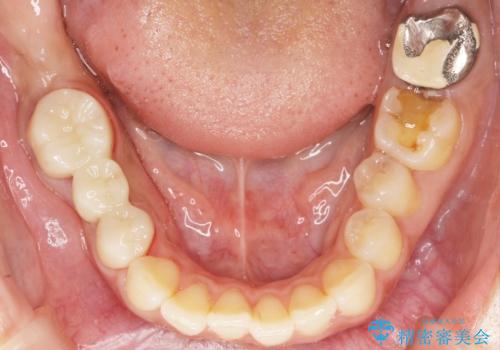

精査したところ、右下の奥歯2本(右下75)は大きなう蝕により歯冠が崩壊し保存不可能な状態でした。

保存不可能な歯を抜去し、オールセラミックのブリッジによる補綴治療を行いました。

プラークコントロール不良につき仮歯を精密に合わせても歯肉の腫脹を認めたため、工夫を凝らして精密な型取りを行うことで適合の良いクラウンを製作致しました。